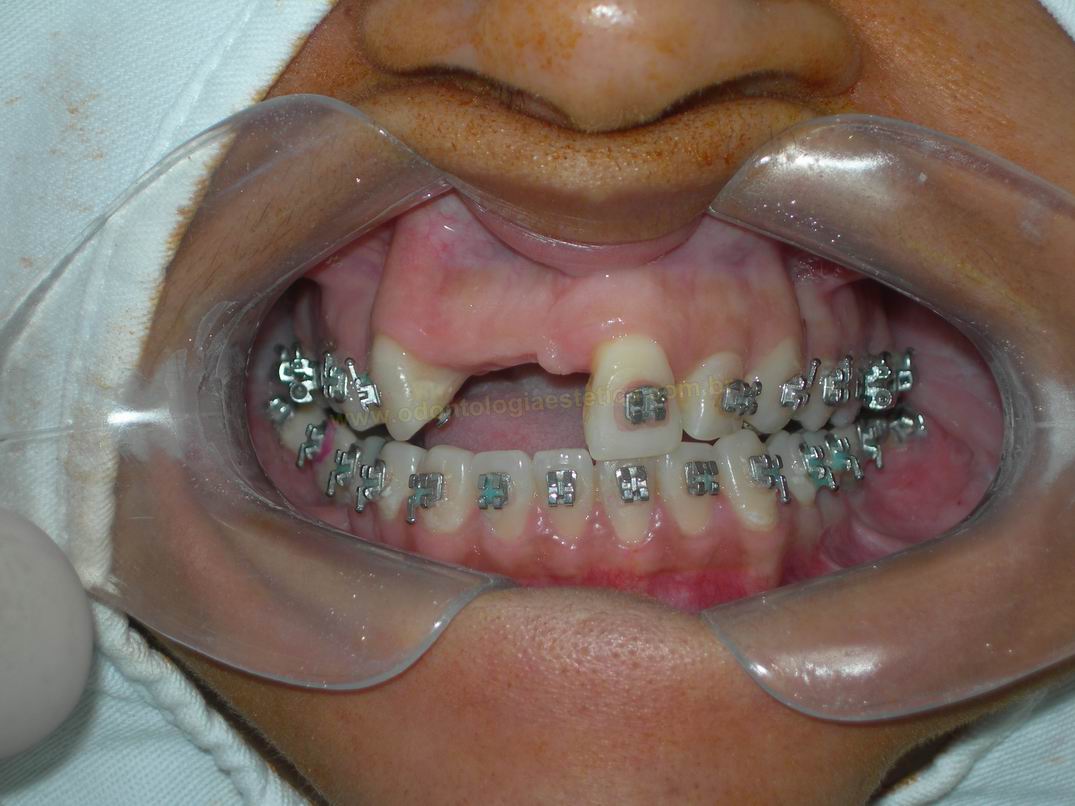

FASE AVANÇADA DO TRATAMENTO ORTODÕNTICO APÓS ABERTURA DE ESPAÇO PARA A INSTALAÇÃO DE DOIS IMPLANTES

FASE AVANÇADA DO TRATAMENTO ORTODÕNTICO APÓS ABERTURA DE ESPAÇO PARA A INSTALAÇÃO DE DOIS IMPLANTES |